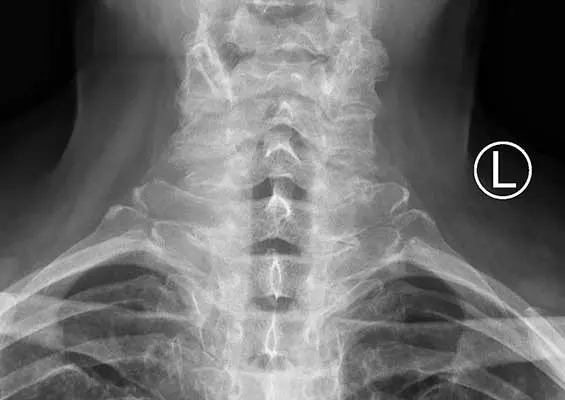

W tym wydaniu m.in.: przeciążeniowy ból piszczeli, czyli shin splints, Diklofenak w leczeniu zesztywniającego zapalenia stawów kręgosłupa, zgoda pacjenta na zabiegi medyczne, rehabilitacja po operacji artrodezy stawu MTP I.